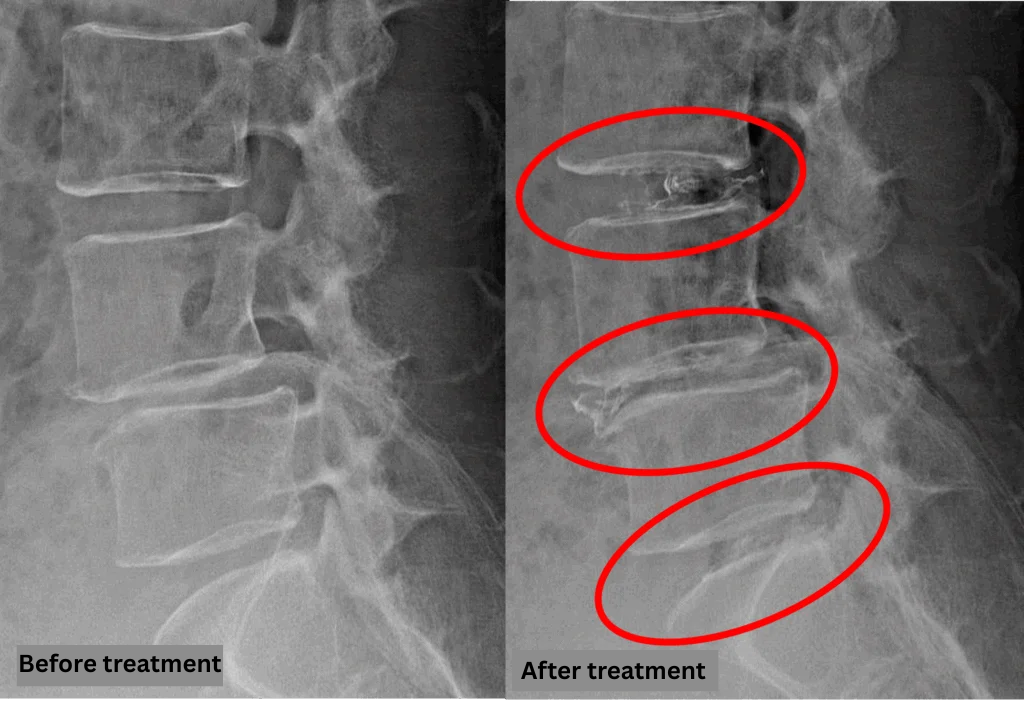

After consulting with the patient, the Cellgel Method was performed on L3/4, 4/5 and 5/s.

After resting in the recovery room, the patient was able to walk home unaided.